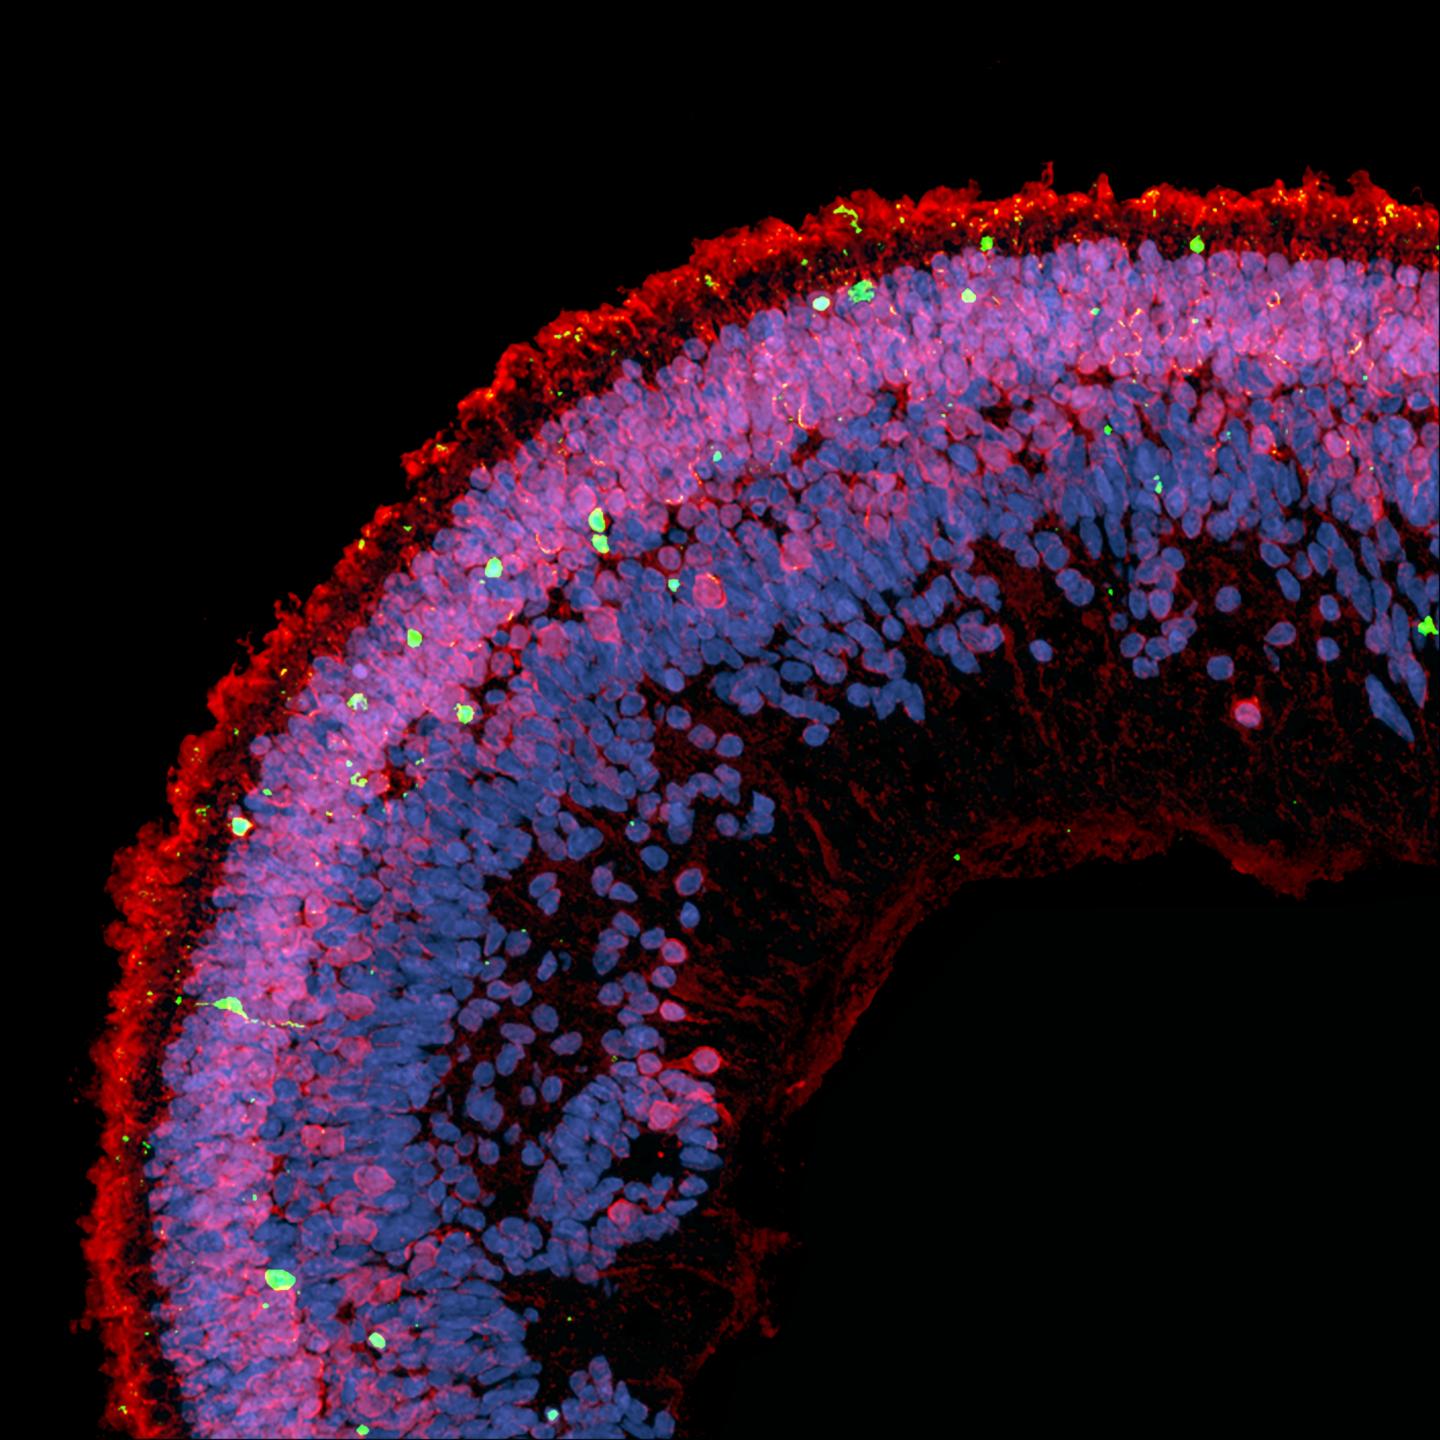

Macular telangiectasia type 2 (MacTel) affects about one in 5,000 people, causing a gradual loss of central vision, typically after age 40. As part of an international research effort directed by the Lowy Medical Research Institute (LMRI) , Bernstein has spent 15 years working with MacTel patients, sifting through family genetic histories.

All HSAN1 patients who did not have clinical signs of MacTel were less than 46 years old and may have been too young to exhibit signs of this late-onset eye disease. Bernstein was able to examine several of these young HSAN1 patients who did not yet show definite signs of MacTel using fluorescence lifetime imaging ophthalmoscopy (FLIO)--an extremely sensitive, non-invasive imaging technology available in the U.S. only at the Moran Eye Center. FLIO images show a characteristic crescent or ring in the macula in all patients affected by MacTel. All of the young asymptomatic HSAN1 patients exhibited the "MacTel signature" in their FLIO images, suggesting that they are at high risk of developing MacTel in the future.

Further research, combining clinical and laboratory studies, showed that many other MacTel patients also had elevated deoxySL levels, presumably due to other genetic defects or low levels of serine, an amino acid that we make and consume in our diets. Elevated levels of deoxySL in the retina were shown to compromise visual function. Low serine and the deoxySLs were not previously known to affect the eye's macular health.